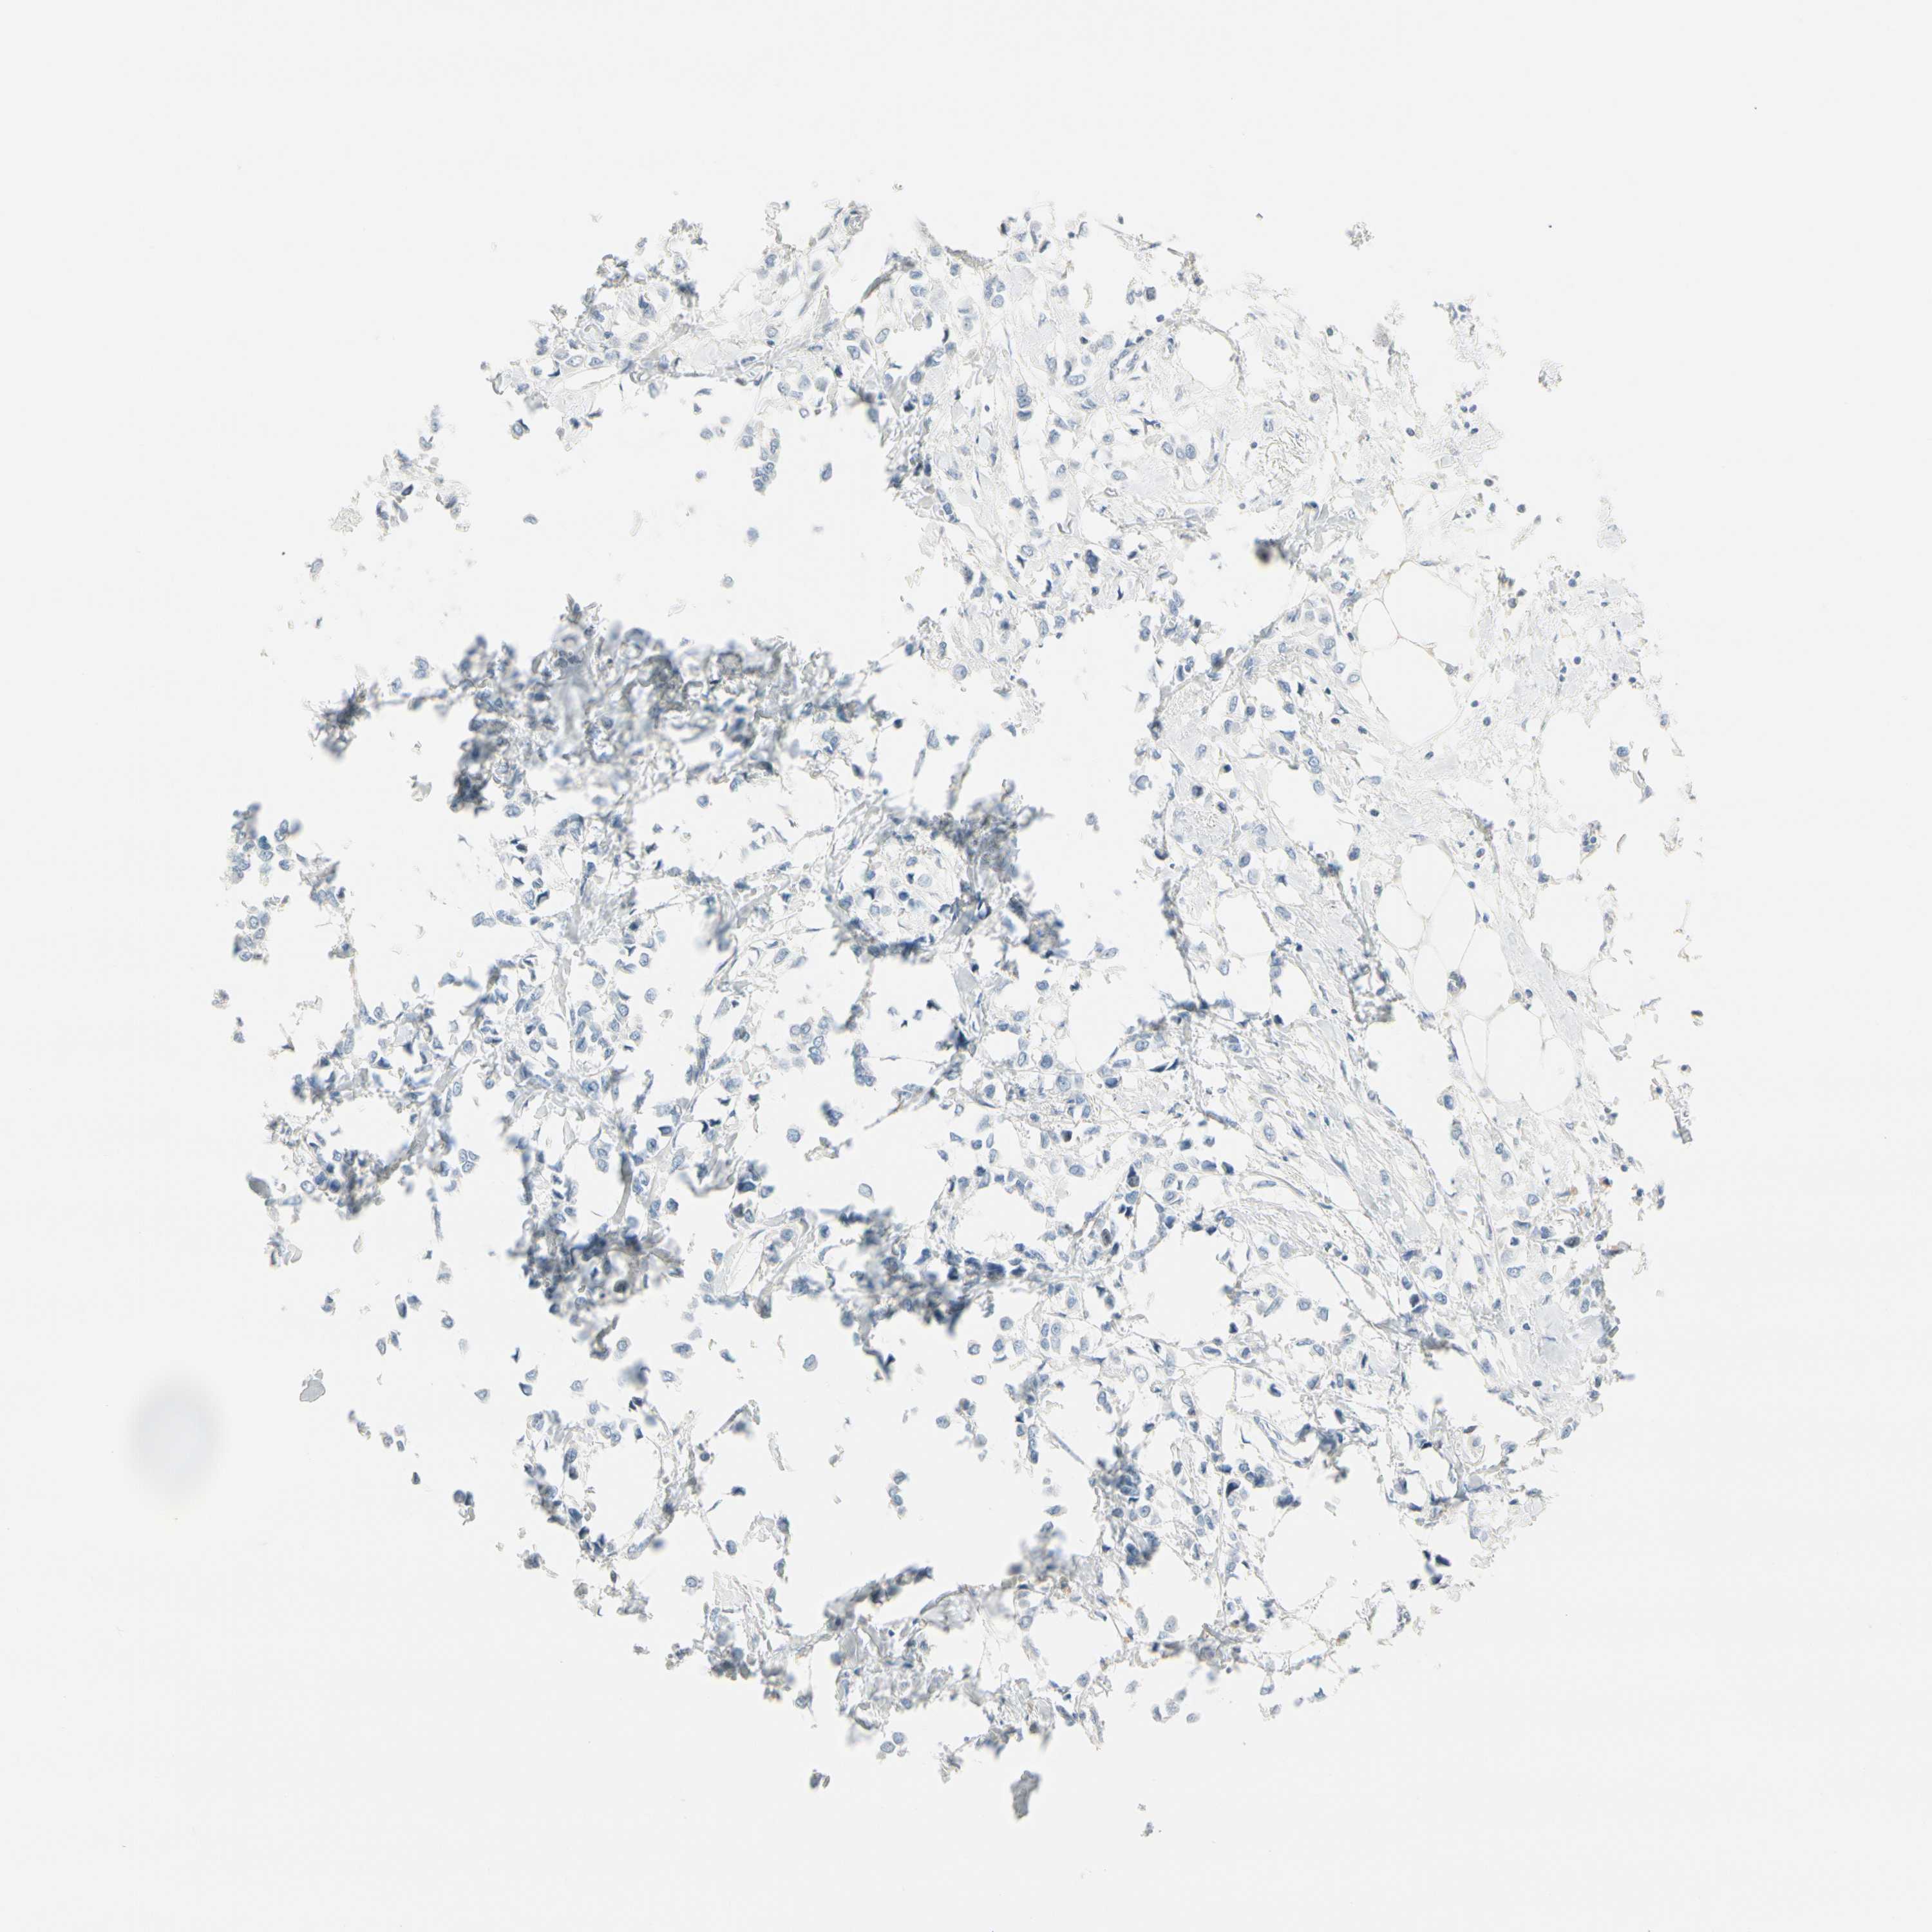

BRCA TCGA BRCA VALIDATION PROTEIN EXPRESSION

ANTIBODIES

AND

VALIDATION